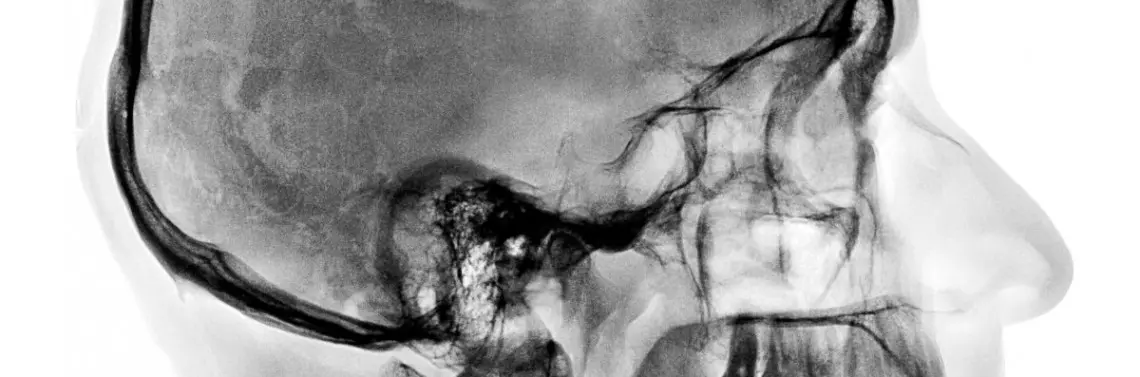

Stawy skroniowo-żuchwowe w osteopatii. Część 2. Informacje specjalistyczne*

W ujęciu osteopatycznym stawy skroniowo-żuchwowe (articulatio temporomandibularis) – podobnie jak każda inna część ciała – rozpatrywane są w odniesieniu do całego organizmu. Z tego powodu w przypadku zaburzeń stawów skroniowo-żuchwowych (SSŻ) na początku badania przeprowadza się ogólne testy służące rozpoznaniu obszarów zaangażowanych w zespół dysfunkcji SSŻ.